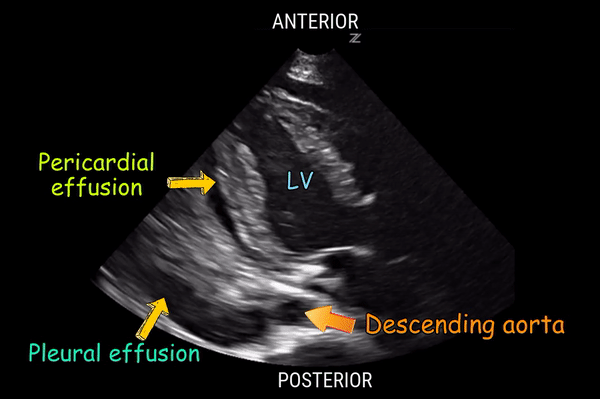

- Pericardial vs pleural effusion on POCUS peristernal long axis (PLAX)

- Pericardial: fluid ANTERIOR to the descending aorta

- Pleural: fluid POSTERIOR to the descending aorta